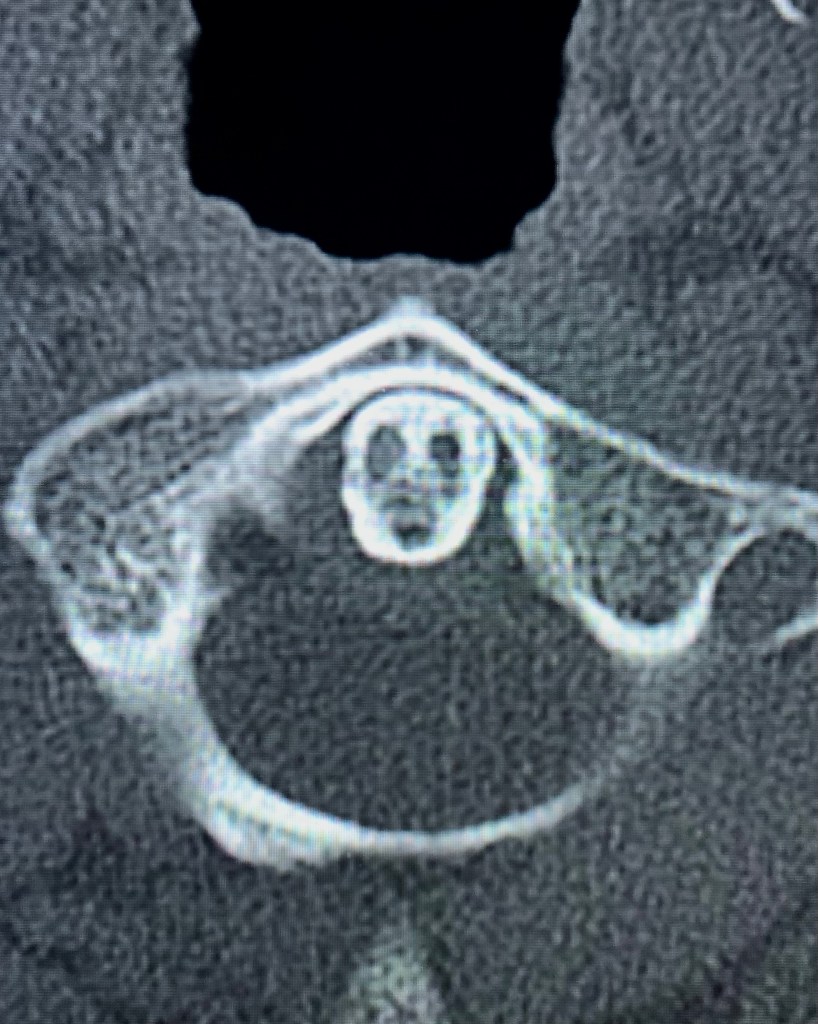

“Phantom Odontoideum”

The odontoid process (the dens) of the C2 vertebra on axial CT image